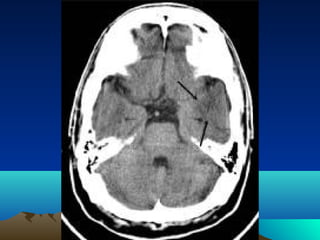

Radiological evaluation

•CT scan

•MRI